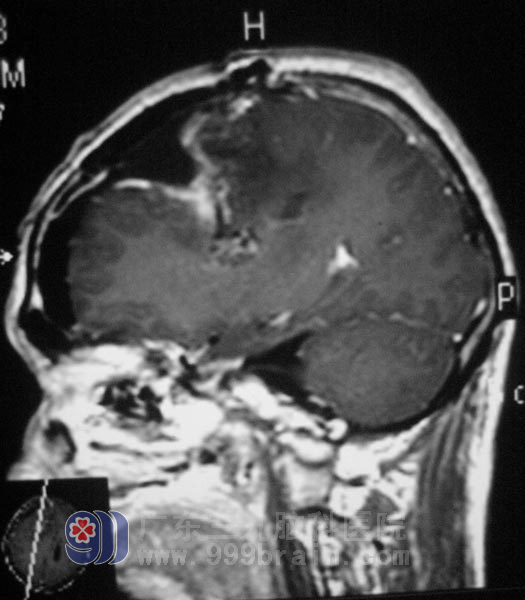

叶叔转至广东三九脑科医院时,已无法自行坐立、行走,双侧眶周轻度肿胀,语言欠流畅,反应、理解能力变差,左侧肢体活动差,轻瘫试验阳性,左侧躯体、肢体痛温觉减弱。头部MRI结果显示:右侧额顶部大脑镰旁窦旁占位,考虑脑膜瘤可能性大,右侧颞叶钩回疝及大脑镰下疝形成。影像见6.6×4.9×6.3cm大小不规则肿瘤影,边界清楚,周围可见“假包膜征”,相邻脑膜可见“脑膜尾征”。病灶向脑组织内突入,邻近顶枕叶、胼胝体、右侧侧脑室体后角受压、变窄。

5月17日,由综合神经外科鲁明主任主刀,行“右额顶部大脑镰旁脑膜瘤切除术”,术中见肿瘤呈灰白色,边界清,血供丰富,肿瘤基底部位于上矢状窦区,侵入窦内。用超声刀在显微镜下分块切除肿瘤,小心切开窦壁,清除窦内肿瘤组织,术腔止血彻底。手术当晚,他恢复清醒,未发生偏瘫,言语流利,回答问题准确,术后病理为:(右侧额顶部)脑膜皮细胞型脑膜瘤,WHO I级。